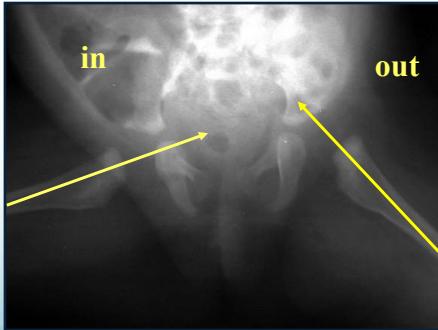

After 3 Months

- More reliable for assessment

- AP abduction view:

- Long axis of femur normally passes through acetabulum

After 6 Months

- Clearly shows dislocation

1. Horizontal Line Through Tri-radiate Cartilage

- Normal: Femoral head ossific center below the horizontal line

- Dislocated: Femoral head ossific center above the horizontal line

2. Perpendicular Line from Acetabular Edge

- Normal: Femoral head ossific center medial to perpendicular line

- Dislocated: Femoral head ossific center lateral to perpendicular line